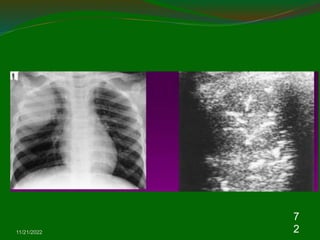

Consolidation

 Irregular hypoechic area of varying size and

shape.

 Echotexure can appear homogenous or

inhomogenous.

 The most common sonographic feature is the

air bronchogram which is characterized by lens

shaped internal echoes within hypodene area

or echogenic lines.

11/21/2022

7

0

1

2

3